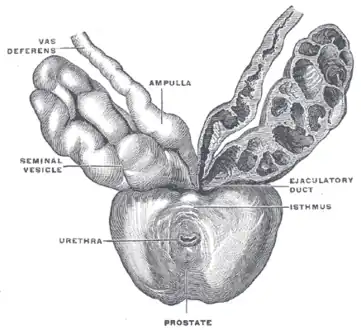

Prostate, urethra, and seminal vesicles.

Prostate, urethra, and seminal vesicles. -